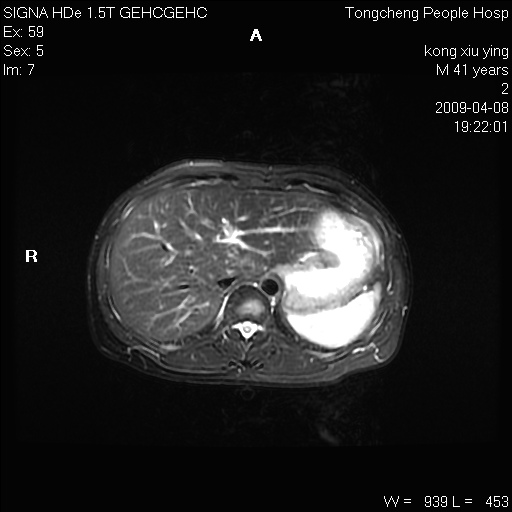

标题: CL1008:【经典】胆囊石榴籽样结石。

女,41岁。健康体检——彩超提示:胆囊显示不清。平素健康,无不适感。

腹部mr扫描及mrcp,图像如下: